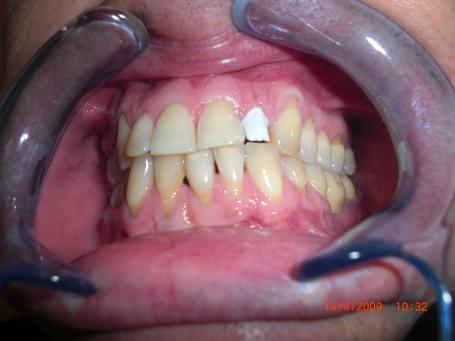

5°)Photo final.

La couronne en zircone est scellée avec un ciment définitif.Le choix de teinte ainsi que l'adaptation gingivale est respectée.